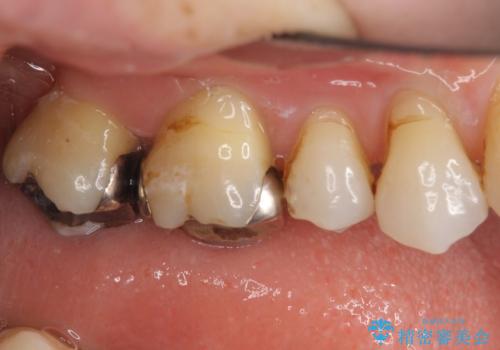

- 銀歯を白くしたいとのことで来院されました。

銀の詰め物を除去した後、その奥にある古い詰め物も除去し完全にむし歯を取り切ったことを確認してからセラミッククラウンを装着していきます。

詰め物の除去後、残った歯が薄い場合は今後の破折リスクを考慮して被せ物での修復処置を提案することがあります。